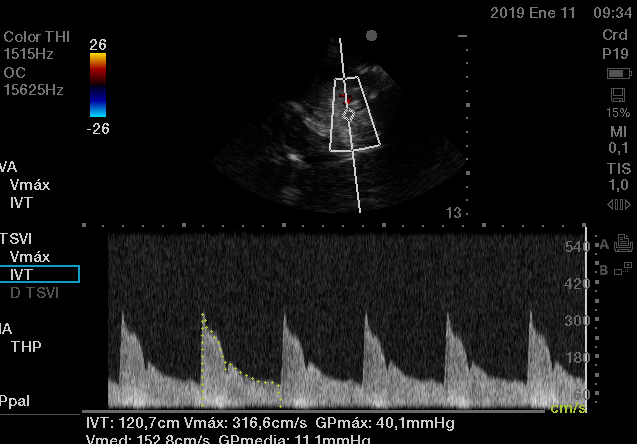

Para estimar los parámetros hemodinámicos de forma no invasiva que obtenemos por métodos más invasivos no exentos de posibles complicaciones inherentes a su colocación, a pie de cama del paciente tales como: PCP, gasto cardíaco, variabilidad del volumen sistólico, PVC, resistencias vasculares sistémicas y pulmonares, agua extravascular pulmonar y guiar las terapéuticas administradas.